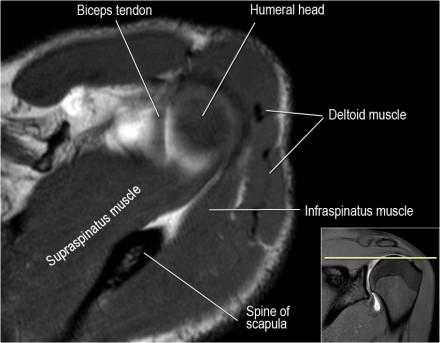

Нормальная анатомия

Нормальная анатомия плечевого сустава в аксиальных изображениях и контрольный список.

- поищите os acromiale, акромиальную кость (добавочная кость, расположенная у акромиона)

- обратите внимание что ход сухожилия надостной мышцы параллелен оси мышцы (это не всегда так)

- обратите внимание что ход сухожилия длинной головки двуглавой мышцы в области прикрепления направлен на 12 часов. Область прикрепления может быть различной ширины.

- обратите внимание на верхние отделы суставной губы и прикрепление верхней плече-лопаточной связки. На данном уровне ищется SLAP-повреждение (Superior Labrum Anterior to Posterior) и варианты строения в виде отверстия под сутавной губой (sublabral foramen - подгубное отверстие). На этом же уровне по задне-боковой поверхности головки плечевой кости визуализируются повреждение Хилл-Сакса.

- волокна сухожилия подлопаточной мышцы, создавая бицепитальную борозду, удерживают сухожилие длинной головки двуглавой мышцы. Изучите хрящи.

- уровень средней плече-лопаточной связки и передних отделов суставной губы. Поищите комплекс Буффорда. Изучите хрящи.

- вогнутость заднебокового края головки плечевой кости не следует путать с повреждением Хилл-Сакса, поскольку это нормальная форма для данного уровня. Повреждение Хилл-Сакса визуализируется только на уровне клювовидного отростка. В предних отделах мы сейчас на урвоне 3-6 часов. Здесь визуализируются повреждение Банкарта и его варианты.

- обратите внимание на волокна нижней плече-лопаточной связки. На данном уровне так же ищется повреждение Банкарта.